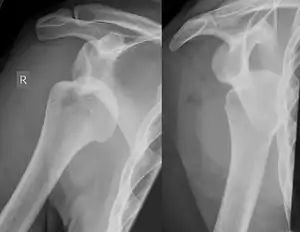

A Hill–Sachs lesion, or Hill–Sachs fracture, is a cortical depression in the posterolateral head of the humerus. It results from forceful impaction of the humeral head against the anteroinferior glenoid rim when the shoulder is dislocated anteriorly.

Diagnosis can be suspected by history and physical examination which is usually followed by imaging. Because of the mechanism of injury, apprehension of anterior dislocation is common with provocative maneuvers. Hill–Sachs lesions have been classified as "engaging" or "non-engaging", with engaging lesions defined by the ability of the glenoid to sublux into the humeral head defect during abduction and external rotation. Engaging dislocations have a higher risk of recurrent anterior dislocation, and their presence can help guide surgical management.[2] Imaging diagnosis conventionally begins with plain film radiography. Generally, anteroposterior (AP) radiographs of the shoulder with the arm in internal rotation offer the best yield while axillary views and AP radiographs with external rotation tend to obscure the defect. However, pain and tenderness in the injured joint make appropriate positioning difficult and in a recent study of plain film x-ray for Hill–Sachs lesions, the sensitivity was only about 20%. i.e. the finding was not visible on plain film x-ray about 80% of the time.[3]

By contrast, studies have shown the value of ultrasonography in diagnosing Hill–Sachs lesions. In a population with recurrent dislocation using findings at surgery as the gold standard, a sensitivity of 96% was demonstrated.[4] In a second study of patients with continuing shoulder instability after trauma, and using double contrast CT as a gold standard, a sensitivity of over 95% was demonstrated for ultrasound.[5] It should be borne in mind that in both those studies, patients were having continuing problems after initial injury, and therefore the presence of a Hill–Sachs lesion was more likely. Nevertheless, ultrasonography, which is noninvasive and free from radiation, offers important advantages.

MRI has also been shown to be highly reliable for the diagnosis of Hill-Sachs (and Bankart) lesions. One study used challenging methodology. First of all, it applied to those patients with a single, or first time, dislocation. Such lesions were likely to be smaller and therefore more difficult to detect. Second, two radiologists, who were blinded to the surgical outcome, reviewed the MRI findings, while two orthopedic surgeons, who were blinded to the MRI findings, reviewed videotapes of the arthroscopic procedures. Coefficiency of agreement was then calculated for the MRI and arthroscopic findings and there was total agreement ( kappa = 1.0) for Hill-Sachs and Bankart lesions.[6]